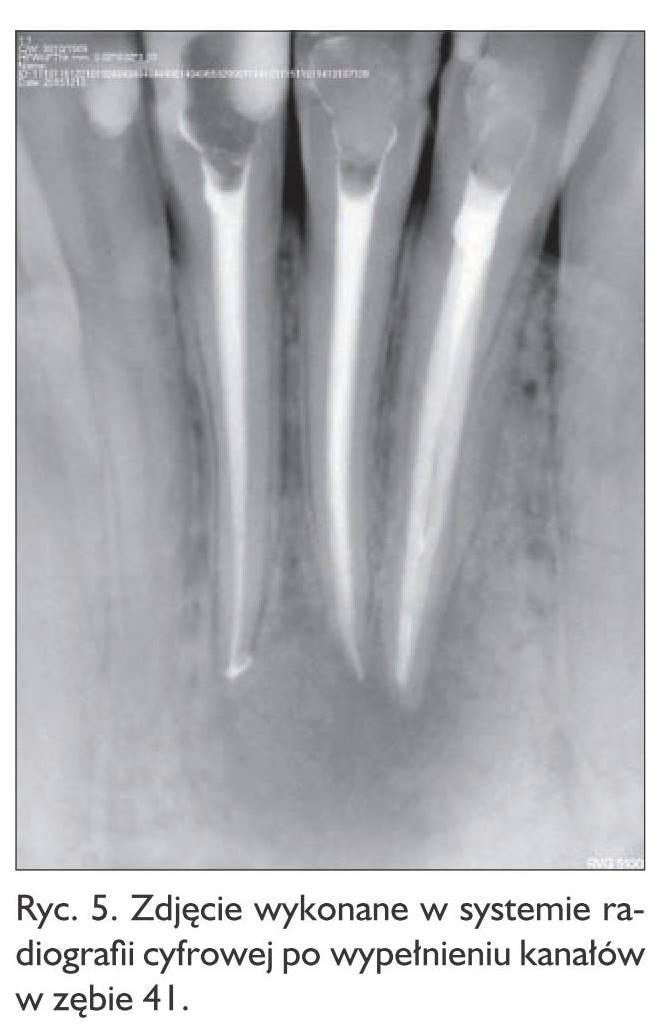

Ze względu na ponowny wyjazd pacjenta umówiono się na kontrolne badanie tomograficzne tej okolicy za 9 miesięcy (grudzień 2015) i podjęcie decyzji co do dalszego leczenia. Pacjent jednak zgłosił się wcześniej (05.11.2015) z powodu silnych dolegliwości bólowych i obrzęku brody. Po badaniu zewnątrz‑ i wewnątrzustnym zdiagnozowano abscessus mentalis. W znieczuleniu miejscowym podanym podskórnie wykonano punkcję terapeutyczną z uzyskaniem dużych ilości treści ropnej. Przepisano Amotaks tabl. à 1 g co 12 godzin oraz założono opatrunek na miejsce wkłucia. Pacjent zgłosił się po dwóch dniach, obrzęk znacznie się zmniejszył, dolegliwości bólowe ustąpiły. Przed planowanym zabiegiem, ze względu na bliskość wierzchołka korzenia zęba 41 oraz brak reakcji na bodziec zimny, ząb poddano leczeniu kanałowemu (ryc. 5) i ustalono termin zabiegu wyłuszczenia torbieli z resekcją wierzchołków korzeni zębów 32, 31, 41.